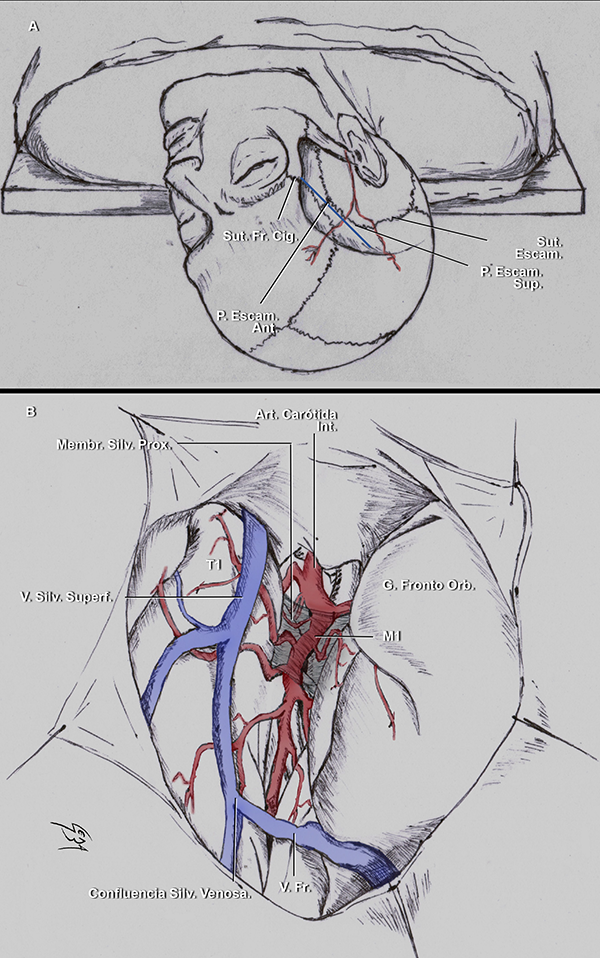

Figura 8:A. La ilustración muestra la posición de la cabeza para una craneotomía pterional derecha. Línea azul: representación de la FS sobre la superficie craneal. B. La ilustración muestra una exposición de la FS a través de una craneotomía pterional izquierda. El punto silviano anterior se localiza 10-15 mm proximal a la confluencia venosa silviana.25,27 Sut: sutura; Escam: escamosa; Fr. Cig: frontocigomática; Ant: anterior; Sup: superior; Membr: membrana; Silv: silviana; Prox: proximal; Art: arteria; Int: interna; V: vena; superf: superficial; Orb: orbitario.

Apertura de la fisura silviana: técnica microquirúrgica

El abordaje pterional es la principal ruta de acceso a esta región, dado que la FS queda expuesta en su epicentro. El mismo puede ser modificado a medida según la localización anatómica precisa dentro del complejo silviano de la patología a ser operada. Para exponer a la porción basal de la FS se precisa el movimiento de extensión de la cabeza del paciente (Figura 5A y 8A). Sin embargo, cuanto más extendida, más inferior se posiciona el techo orbitario y, consecuentemente, más obstruida estará la visión de lesiones cerca de la base del cráneo; así como también, la visión necesaria para realizar una clinoidectomía anterior. La orientación diagonal ascendente de la porción lateral de la FS, justifica la necesidad de rotar la cabeza del paciente (Figura 5A y 8A).

Luego de realizada la craneotomía y durotomía, se identifica a la FS. En algunos casos la fisura se reconoce fácilmente. Cuando no sucede, es útil valerse de las venas silvianas como reparos anatómicos para identificarla. Las venas temporales y frontales drenan en las venas silvianas superficiales, que cursan sobre la parte lateral de la FS (Figura 8B y 10A). También, todas las arterias M4 nacen de la fisura y se dirigen centrífugamente hacia la corteza cerebral (Figura 9C). Consecuentemente, si estos vasos son recorridos desde distal a proximal, el cirujano siempre encontrará a la fisura. Es por esto que se dice que “los vasos son nuestros aliados”. No existen vasos arteriales que crucen de lado a lado, con orientación perpendicular a la FS. Si una arteria aparentase tener dicha dirección, el cirujano debería disecarla cuidadosamente, identificar de qué ramo nace, y luego apartarla a su lado frontal o temporal, según corresponda.

Durante la cirugía, con la membrana aracnoidea intacta, no es fácil identificar las estructuras anatómicas como se hace en los especímenes cadavéricos disecados. Es por esto que los cirujanos pueden usar como punto de referencia para localizar al punto silviano anterior al área más prominente y anterior del giro frontal inferior que se continúa, luego de un borde agudo, con la superficie basal del cerebro. Esta área prominente es la pars orbitalis (Figura 9A). Los giros frontoorbitarios y la superficie basal de la FS solamente son expuestos luego de que el ala menor del esfenoides es removida. Unos pocos milímetros posteriores a esta área, uno puede asumir con seguridad que se localiza la pars triangularis. Más aún, la punta de la pars triangularis suele apuntar a un ensanchamiento prominente de la FS: el punto silviano anterior (Figura 3). También, dado que el punto silviano anterior se localiza donde la fisura silviana pasa de la superficie basal a la lateral, ubicar el sitio donde la fisura cambia de sentido, es otra forma de encontrar este punto microquirúrgico. Finalmente, cuando la parte superficial de la FS está deformada porque el opérculo frontal indenta al temporal, o viceversa, o, cuando la membrana aracnoidea es particularmente opaca, el neurocirujano debe localizar la unión de la vena superficial temporal con la frontal. Este punto es nombrado en la literatura como “confluencia venosa silviana”. El punto silviano anterior se localiza unos milímetros proximales a la confluencia venosa silviana (Figura 8B y 10A).

Los autores comienzan a disecar la FS en el punto silviano anterior debido a que allí se encuentra una “subcisterna” aracnoidea natural generada por una retracción espontánea de la punta de la pars triangularis (Figura 5A). Además, la orientación oblicua inferior en el plano coronal del plano polar del lóbulo temporal (Figura 11C y D), así como también, su dirección lateromedial, contribuyen a la amplificación del espacio subaracnoideo en este punto microquirúrgico esencial. Para acceder a las cisternas aracnoideas basales, la fisura es disecada desde la superficie lateral a la basal. Solo cuando es necesario, las cisternas carotídeas, interpeduncular y quiasmática son abiertas previamente. Esto es útil, por ejemplo, cuando hay hipertensión intracraneal debido a la ruptura de un aneurisma, y se precisa bajar la tensión para realizar la disección. Debe ser tenido en cuenta que para liberar una cantidad considerable de líquido cefalorraquídeo (LCR) con este propósito, es recomendable abrir la cisterna carotídea, así como también la interpeduncular, a través de la disección de la membrana de Liliequist. La cisterna carotídea es una cisterna relativamente pequeña, que, si es abierta aisladamente, solo liberará una pequeña cantidad de LCR.

Con una hoja de bisturí N 11, y retrayendo gentilmente el opérculo con una cánula de aspiración delicada con mínima presión de succión, se incide la membrana aracnoidea, preferiblemente en el lado frontal de la vena silviana superficial (Figura 10A). Consecuentemente, de necesitarse retraer el lóbulo frontal con una espátula, las venas serán mejor preservadas. El cirujano debe siempre intentar preservar el drenaje venoso. Sin embargo, solo si es imperativo las venas silvianas pueden ser coaguladas. No se debe usar sistemáticamente retractores estáticos. El uso de pequeños algodones permite una suave separación de las estructuras cerebrales con mínima presión (Figura 10B). Más aún, cuanto más se expone al lóbulo temporal en la craneotomía, más simple será abrir la fisura. Así también, cuanto más se drilla la pared lateral y techo de la órbita y el ala menor del esfenoides, será necesaria menor retracción cerebral y se conseguirá más exposición de la parte basal. Continuando desde el punto de inicio, las membranas aracnoideas son incididas con una hoja de bisturí o con microtijeras.

El primer compartimiento silviano que es disecado desde el punto silviano anterior es el compartimiento opercular anterior. La mayoría de las FS tienen un compartimiento opercular anterior curvilíneo irregular. Esto se debe frecuentemente a una pars orbitalis prominente que indenta y comprime al plano temporal. Una vez que este compartimiento es disecado, si el cirujano continúa proximalmente y en profundidad por la fisura, se accede al compartimiento esfenoidal. Con una cánula de aspiración delicada con mínima presión de succión, pinzas bipolares bayonetada y microtijeras, se progresa la disección.

Las ramas y segmentos de la ACM no siempre se identifican con claridad. En función de poder hacerlo, es útil disecar los vasos arteriales desde distal a proximal hasta que la bifurcación carotídea es identificada, y luego seguir a la ACM en dirección opuesta, de proximal a distal. M1 debe ser disecada por su cara anterior. Esto es porque las arterias lenticuloestriadas usualmente nacen de su cara superior o posterosuperior (Figura 1C,10C, 10D).

El límite medial de la cisterna silviana es la membrana silviana proximal que tiene un color blanco perlado y es opaca (Figura 8B y 10E). Se accede a la cisterna carotídea cuando esta membrana es abierta (Figura 10F). La bifurcación carotídea y los segmentos proximales de M1, A1 y sus ramas supraclinoideas, se ubican en la cisterna carotídea (Figura 1D y 10G). Esta cisterna se relaciona inferiormente con el segmento anterior del uncus y superiormente con el trígono olfatorio y el giro recto. La cisterna carotídea es un punto de encrucijada de las cisternas basales. Desde ella se puede alcanzar al tercer ventrículo a través de la lámina terminalis, a la cisterna carotídea contralateral, e incluso a la fosa posterior, a través de la apertura de la membrana de Liliequist, hacia la cisterna interpeduncular.

En este punto, es recomendable trabajar por la cara lateral de la carótida, en el espacio carotido-oculomotor. El espacio óptico-carotídeo, en la cara medial de la arteria carótida interna (ACI), tiene mayor número de arterias perforantes. Las arterias perforantes que corren paralelas a la ACI, se dirigen a la SPA. En cambio, las que irrigan al infundíbulo y al quiasma óptico, tales como la arteria hipofisaria superior, tienen un curso perpendicular a la ACI.

Membranas silvianas

En un completo estudio de Inoue et al.,28 se describe a la cisterna silviana limitada por la membrana aracnoidea externa y la piamadre. Numerosas trabéculas y membranas internas cruzan a lo largo de ella, dividiendo al espacio subaracnoideo en compartimientos más pequeños (Figura 2).

Las membranas aracnoideas intrasilvianas de la cara lateral de la FS son esquematizadas en 3, acorde a la literatura:28 la membrana lateral, intermedia y medial. La membrana silviana lateral es la más superficial. El trayecto de las venas silvianas superficiales y el segmento M4 de la ACM se ubica entre esta membrana y la membrana aracnoidea externa. Se adhiere a los márgenes laterales de los opérculos frontoparietotemporales. La membrana silviana intermedia se relaciona con la porción medial de los opérculos y se localiza lateral al segmento M2. La membrana silviana medial es la más profunda de todas y se localiza medial a M2. Está adherida al margen más profundo del opérculo frontoparietal y la corteza insular (Figura 2).28

La membrana aracnoidea silviana intermedia divide arbitrariamente al aspecto lateral de la cisterna silviana en dos compartimientos.28 Medial a esta membrana, se ubica la hendidura insular lateral. Las venas silvianas profundas y el segmento M2 se localizan en este compartimiento. Lateral a la membrana silviana intermedia, se encuentra el compartimiento opercular lateral (Figura 2).

Puntos microquiúrgicos silvianos

Los puntos microquirúrgicos silvianos tienen su correlación con puntos craneométricos. Los mismo fueron popularizados por Ribas en varias publicaciones.22,23,29 El punto silviano anterior15,17,22,23,25,29 se relaciona en la superficie craneal, con un punto localizado 3 cm detrás de la sutura frontocigomática.23,29 Este punto craneométrico también se lo puede ubicar en el punto más anterior de la sutura escamosa, sitio donde las suturas esfenoescamosa, esfenoparietal y escamosa se entrecruzan. Ribas et al.29 nombró a este punto craneométrico: punto escamoso anterior (Figura 14).

El punto rolándico inferior se ubica 2 cm detrás del punto silviano anterior.29 Se relaciona superficialmente con el punto craneométrico llamado punto escamoso inferior,29 que se localiza en el punto más superior de la sutura escamosa. El punto escamoso inferior también puede ser ubicado 4 cm superior, en línea vertical, a la depresión preauricular. Así la FS se proyecta sobre una línea que conecta el canto lateral ocular, con los puntos escamosos anterior e inferior (Figura 8A).